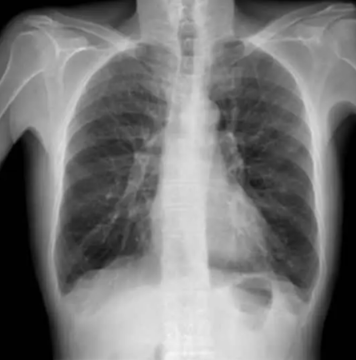

Bronquitis crónica | EPOC El glutatión como regulador clave del estrés oxidativo y la inflamación pulmonar Leer más